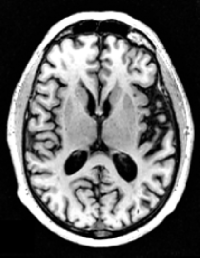

In this study, we use the baseline 1.5T T1-weighted MRI images of subjects from the ADNI-1 dataset [10]. The volumetric 3D MPRAGE protocol is used to acquire sagittal T1-weighted MRI images with an in-plane spatial resolution of 1.25×1.25mm21.251.25superscriptmm21.25\times 1.25~{}\mathrm{mm}^{2} and 1.2 mm thick sagittal slices. The imaging dataset contains baseline images from 695 participants including 200 Alzheimer’s disease, 231 cognitively normal, 164 progressive MCI, and 100 stable MCI. Figure 5 shows four samples from this dataset, and Table 1 presents the demographic and clinical information of subjects in ADNI-1.

Figure 5: Four samples from ADNI-1 dataset [10] (a) AD, (b) CN, (c) pMCI, and (d) sMCI